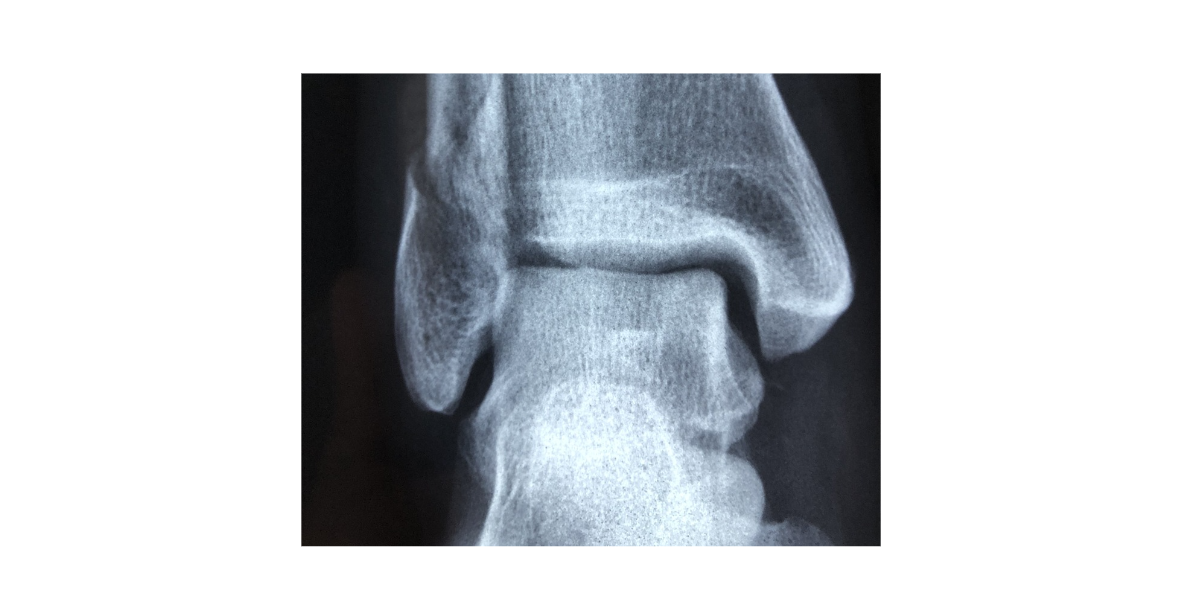

퇴행성 발목관절염은 관절의 연골이 서서히 닳아 없어지면서 뼈와 뼈 사이의 마찰이 증가하고, 결국 염증과 통증, 운동 제한까지 유발하는 만성 질환입니다. 무릎이나 고관절처럼 흔하게 인식되진 않지만, 실제로 발목 관절은 체중을 지탱하는 중요한 구조로서 기능적 손상이 발생할 경우 삶의 질 저하가 매우 큽니다. 특히 발목은 전방위적인 움직임을 요구하는 부위이기 때문에 퇴행성 변화가 발생하면 일상생활 속 걷기, 서기, 계단 오르기 등이 어려워집니다. 본 글에서는 발병 원인, 증상의 특징, 그리고 효과적인 치료방법까지 깊이 있게 살펴보겠습니다.

퇴행성 발목관절염의 증상은 서서히 시작되며 점진적으로 악화되는 양상을 보입니다. 가장 먼저 나타나는 증상은 통증이며, 이는 주로 활동 후에 뚜렷하게 느껴집니다. 오래 걷거나 계단을 오르내린 후에 발목이 욱신거리거나 무겁게 느껴진다면 단순 피로가 아닌 초기 관절염일 수 있습니다. 이 통증은 휴식을 취하면 일시적으로 완화되지만, 병이 진행되면 휴식 중에도 통증이 지속되거나 수면에 방해가 되는 경우도 발생합니다. 또한 발목의 움직임에 제한이 생기고, 특정 방향으로 발목을 돌릴 때 뻣뻣함이나 불편함이 증가합니다. 아침에 일어났을 때 발을 바닥에 디디는 것이 힘들거나, 움직일 때 ‘뚝뚝’하는 소리가 나는 것도 퇴행성 관절염의 대표적인 징후입니다. 관절 내 연골이 손상되면서 뼈와 뼈 사이 마찰이 직접적으로 발생해 이 같은 마찰음이 나는 것입니다. 부종 역시 빈번히 동반되는 증상입니다. 관절 내 염증 반응이 활성화되면 발목이 붓고 누르면 통증이 발생하며, 부종은 신발을 신기 어렵게 만들거나 보행 자세에 영향을 미칩니다. 염증이 심할 경우 붉은 기운과 열감이 동반되기도 합니다. 이와 함께 발목 관절이 비대칭적으로 변형되기도 하며, 무릎이나 허리로 통증이 전이되는 2차 통증이 발생할 수 있습니다. 만성화되면 통증에 대한 두려움으로 인해 활동량이 감소하고, 이로 인해 근력이 약화되어 관절이 더 불안정해지는 악순환이 생깁니다. 특히 균형감이 저하되어 낙상 위험이 높아지며, 고령자에게는 골절로 이어질 위험도 존재합니다. 따라서 일상생활 중 발목에 반복적인 불편함이나 통증이 있다면 반드시 전문 진단을 받아보는 것이 필요합니다.